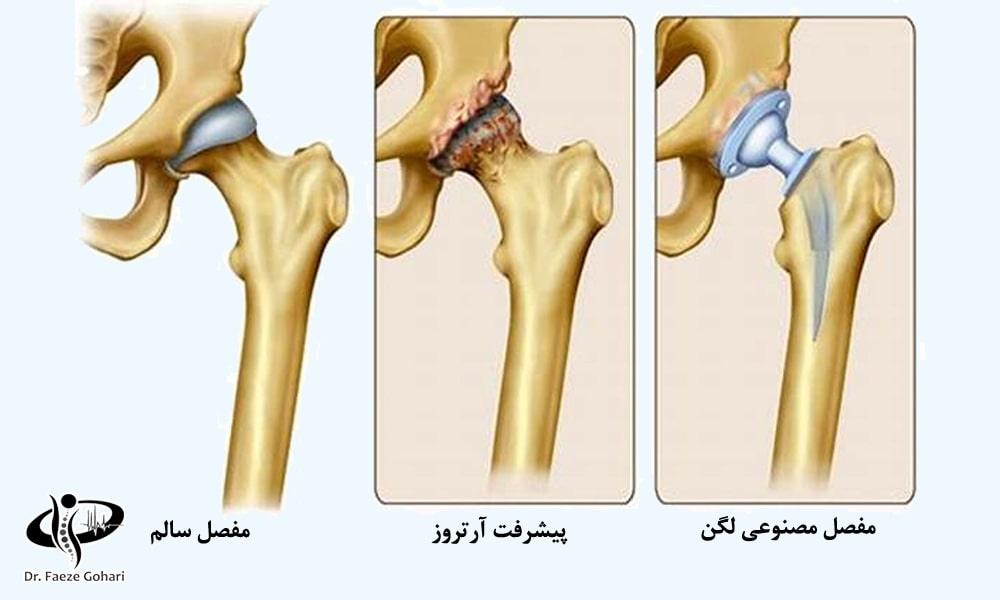

آرتروز لگن (استئوآرتریت لگن) به معنای فرسایش و آسیب مفصل لگن ناشی از تخریب غضروف است. این بیماری میتواند در یک یا هر دو طرف لگن رخ دهد و در صورت عدم درمان مؤثر، بهتدریج پیشرفت کرده و فرد ممکن است نیاز به جراحی تعویض مفصل پیدا کند.

تزریق سلولهای بنیادی و پیآرپی در آرتروزهای خفیف تا متوسط میتواند به بازسازی و ترمیم غضروف آسیبدیده کمک کند. در صورت تشکیل زائدههای استخوانی (استئوفیتها)، سلولدرمانی میتواند روند پیشرفت آنها را کند کرده، التهاب و درد را کاهش دهد و عملکرد مفصل را بهبود بخشد، اما قادر به حذف کامل زائدههای ایجادشده نیست. در مراحل پیشرفته آرتروز که غضروف به طور کامل تخریب شده است، این روشها بهعنوان یک درمان کمکی پس از جراحی برای بهبود بافتهای اطراف مفصل و تسریع روند بازتوانی استفاده میشوند. در ادامه، مواردی که سلولدرمانی در آنها انجام میشود، ذکر شده است.

سلولدرمانی میتواند در به تأخیرانداختن جراحی یا جایگزینی آن در مراحل ابتدایی آرتروز کمک کند، اما در آرتروز پیشرفته یا تخریب شدید غضروف، ممکن است همچنان نیاز به جراحی تعویض مفصل باشد.

درمان آرتروز لگن با جراحی چگونه است؟

در عمل جراحی تعویض مفصل استخوانهای تشکیلدهنده مفصل از بدن خارج شده و با اجزاء مصنوعی جایگزین میشوند.